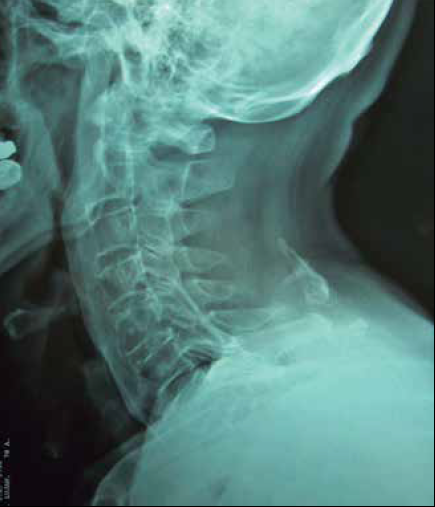

Figura 2 Radiografía lateral de columna cervical de varón de 46 años, con 25 años de trabajo de estibador, la cual muestra: miositis osificante circunscrita de C4 a C6, en ligamento nucal en la inserción ligamentaria de ambos trapecios, al igual que en vértice de apófisis espinosa de C7.